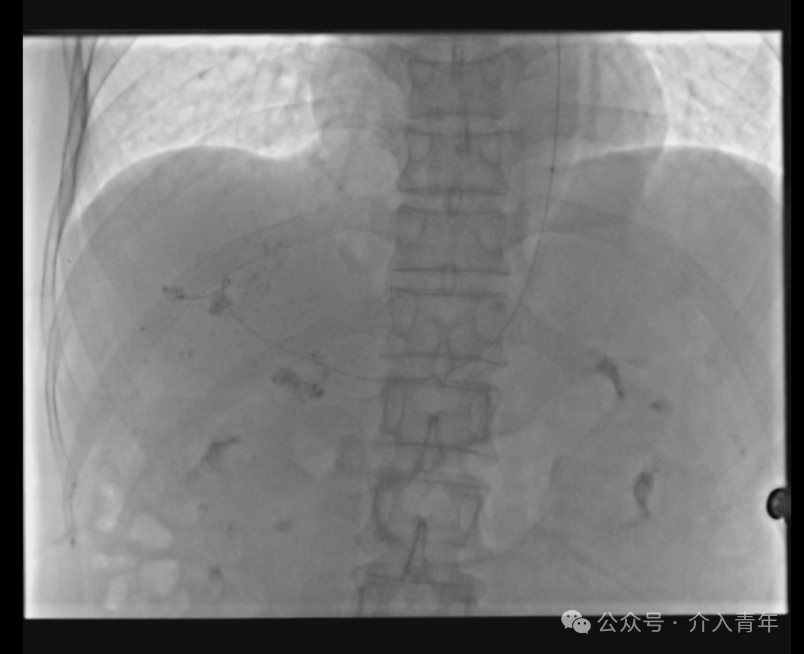

微导丝超选入肝动脉远端固定,交换出造影导管,通过长导丝置入微导管,退出导丝术式即成(交换操作均由笔者单人完成,当然双人会更好完成)。

术后的包扎固定特别简洁,微导管盘成一圈,一张敷贴即可完全覆盖。

相信很多同道会疑问单微导管置管的稳定性是否可以保证,这个问题见仁见智,有专家认为微导管的置管反而更加稳定,笔者也持相同观点,毕竟造影导管顺应性差,后方的旋转拉伸的力量都容易传导到前方,微导管的力量则不易传导过去,可以储存一定的张力。